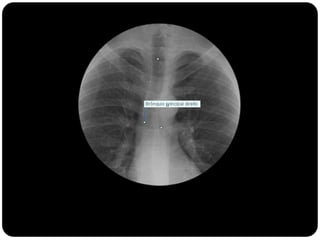

BRÔNQUIOS

PRINCIPAIS

LOBARES

SEGMENTARES

 Brônquios principais originam-se da traquéia

na carina;

 Brônquio direito: ângulo mais obtuso com o

eixo longo da traquéia;

 Direito(2,2cm) mais curto que o

esquerdo(5cm);